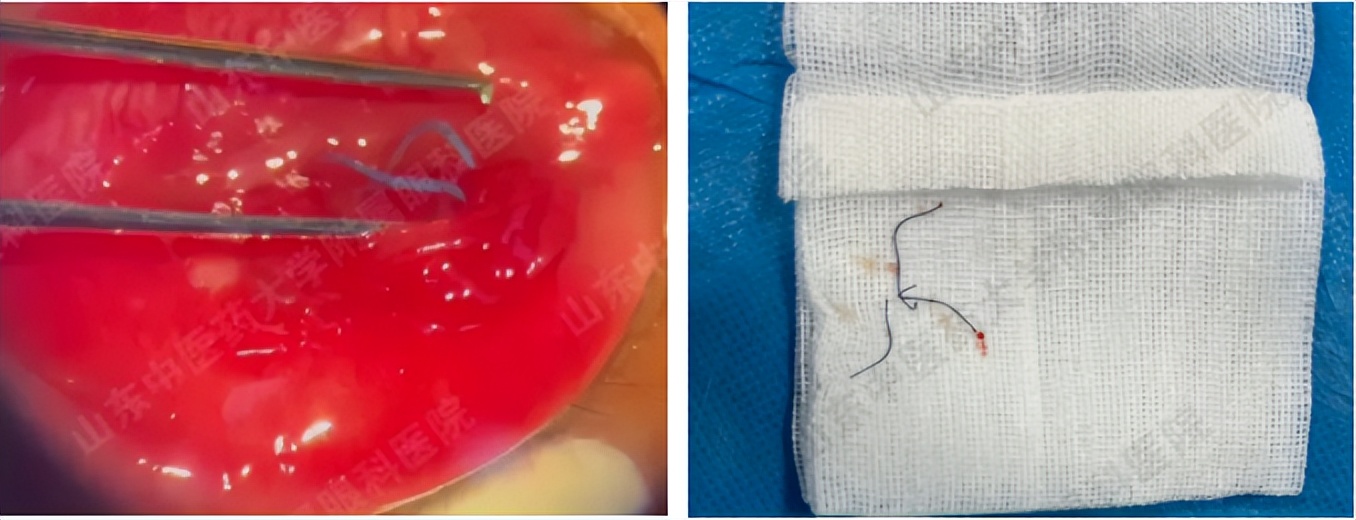

▲ 翻开上眼皮发现,结膜穹窿部(深处)见蓝色粗大缝线(对比右眼,左眼上睑结膜肉芽增生)

▲ 3条缝线全都外露

经表面麻醉下,原越医生将缝线拆除,但是发现不仅1条缝线,而是3条缝线全都暴露在外面!